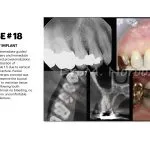

A natural tooth consists of a root and a crown. If you compare natural teeth to implant-supported replacement teeth, you’ll see they have the same basic parts.